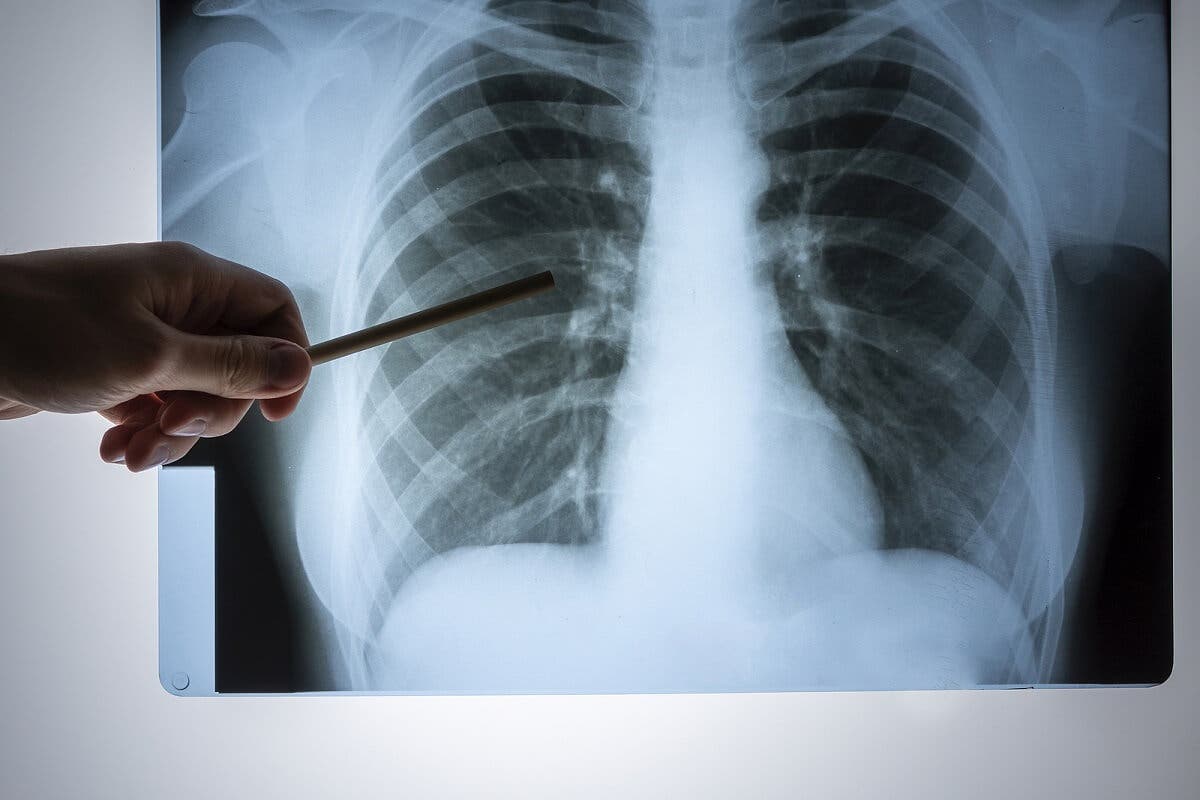

Respiratoriske prosesser som forårsaker smerte på høyre side av brystet

I denne delen vil vi dekke noen tilstander i pleura som er i stand til å utløse smerter i høyre side av brystet. Pleura er en struktur dannet av to lag: den viscerale og den parietale. Det er i sistnevnte at den innerveringen som er nødvendig for å overføre smerte er funnet.

Høyresidig lungebetennelse

Infeksjon av lungevevet utgjør lungebetennelse, som er en alvorlig enhet som krever umiddelbar medisinsk vurdering. Symptomer inkluderer følgende:

- Hoste

- Feber

- Generelt ubehag

- Åndenød

Hvis den infeksjonsmessige prosessen er lokalisert i høyre lunge, kan smerte oppstå på den siden av brystet. En grundig fysisk undersøkelse og komplementære tester er nødvendig for å etablere en effektiv og rettidig behandling.

Høyre pneumothorax

Tilstedeværelsen av luft mellom lagene i pleura er kjent som pneumothorax. Selv om en skade kan forårsake det, inkluderer andre mulige årsaker visse medisinske prosedyrer og til og med spontan ruptur av et skjørt område i pleura.

Pneumothorax er assosiert med plutselige smerter på den berørte siden og kortpustethet. Behandling avhenger av alvorlighetsgraden av det kliniske bildet.

Tumorprosesser som årsaker til høyresidig brystsmerter

Tumorer lokalisert i høyre lunge er en annen årsak til høyresidig brystsmerter, men når disse tilstandene er lokalisert i lungevevet, er de vanligvis asymptomatiske i de innledende stadiene fordi de ikke involverer parietal pleura.

I disse tilfellene er det viktig å spørre om vekttap, tobakksbruk og kronisk eksponering for asbest og biomasserøyk. I tillegg til smerter er hoste og kortpustethet vanlig.

Andre årsaker til pleurittisk smerte

Betennelse i pleura, også kalt pleuritt, er en annen mulig kilde til høyresidig brystsmerter. Smerten forsterkes vanligvis ved hoste og dyp pust.